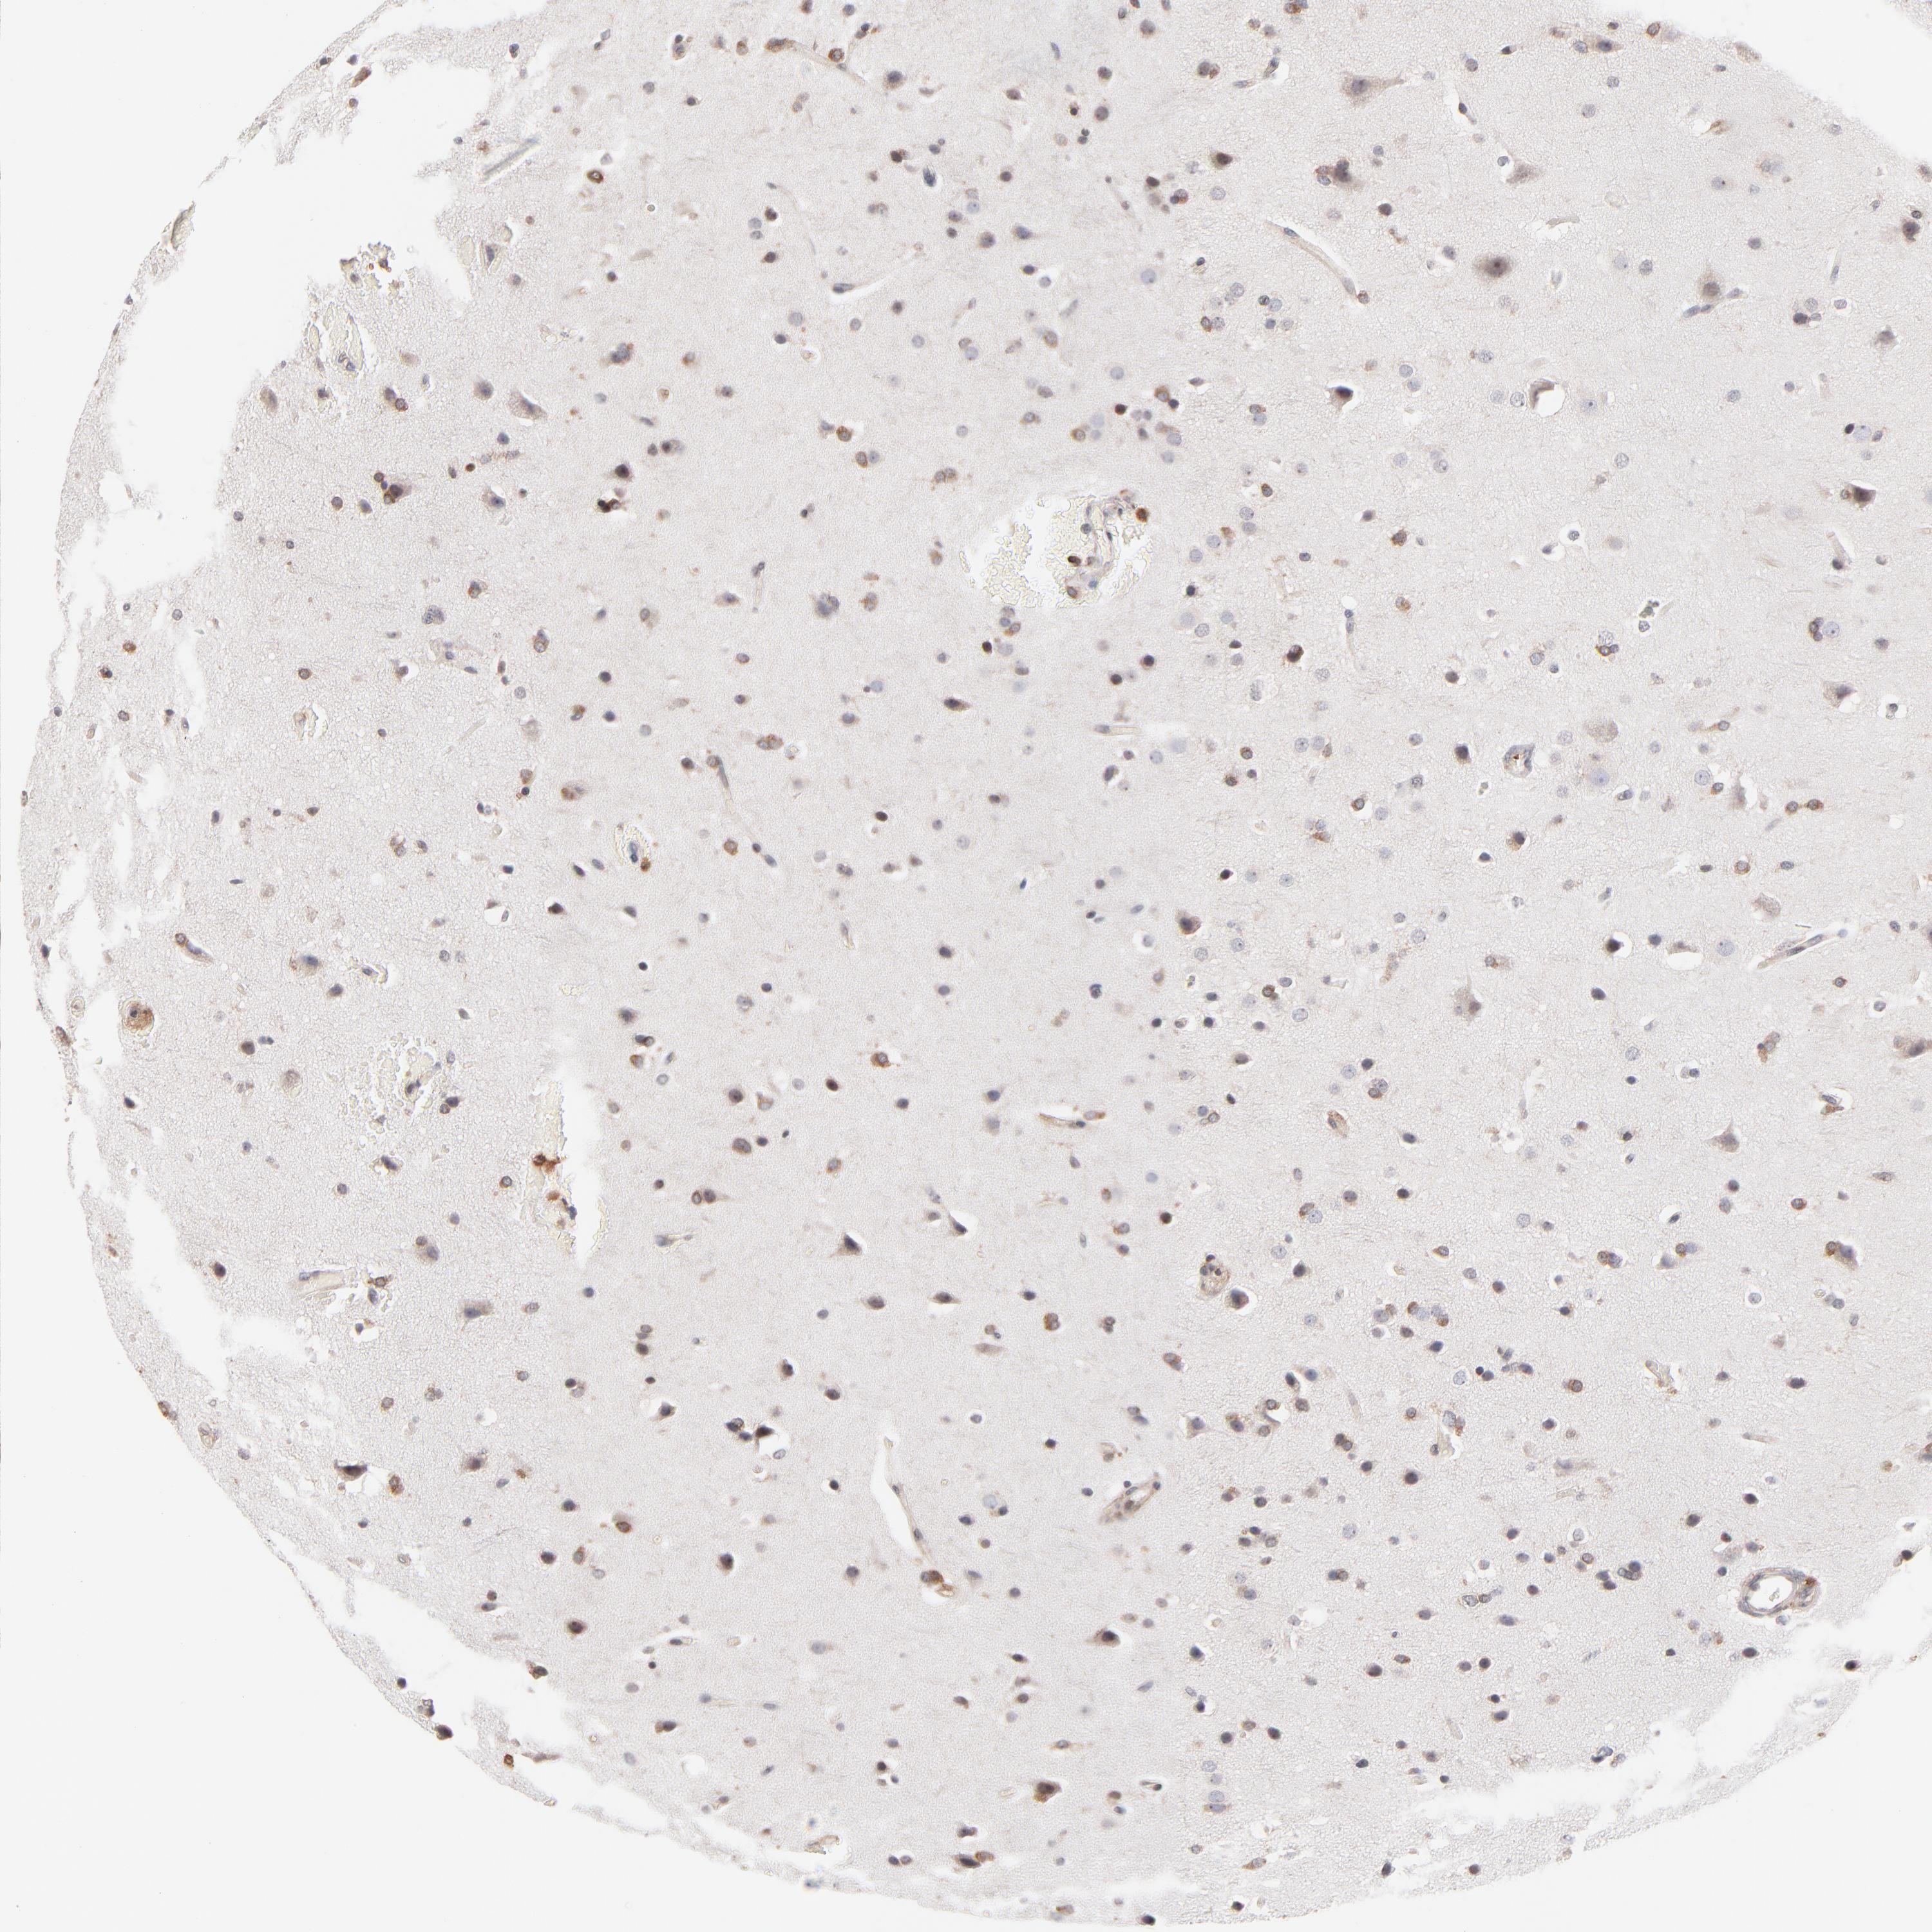

GLIOMA - Protein expressioni

A mouse-over function shows sample information and annotation data. Click on an image to view it in a full screen mode. Samples can be filtered based on level of antibody staining by selecting one or several of the following categories: high, medium, low and not detected. The assay and annotation is described here.

Note that samples used for immunohistochemistry by the Human Protein Atlas do not correspond to samples in the TCGA dataset.

Antibody stainingi

Antibody staining in the annotated cell types in the current human tissue is reported as not detected, low, medium, or high, based on conventional immunohistochemistry profiling in selected tissues. This score is based on the combination of the staining intensity and fraction of stained cells.

Each image is clickable and will lead to virtual microscopy that enables deeper exploration of all samples and also displays staining intensity scores, fraction scores and subcellular localization as well as patient and tissue information for each sample.

Antibody HPA003739

Antibody CAB009737

Staining

High

Medium

Low

Not detected

Intensity

Strong

Moderate

Weak

Negative

Quantity

>75%

75%-25%

<25%

None

Location

Nuclear

Cytoplasmic/membranous

Cytoplasmic/membranous,nuclear

Glioma, malignant, High grade

Glioma, malignant, Low grade

Glioma, malignant, NOS